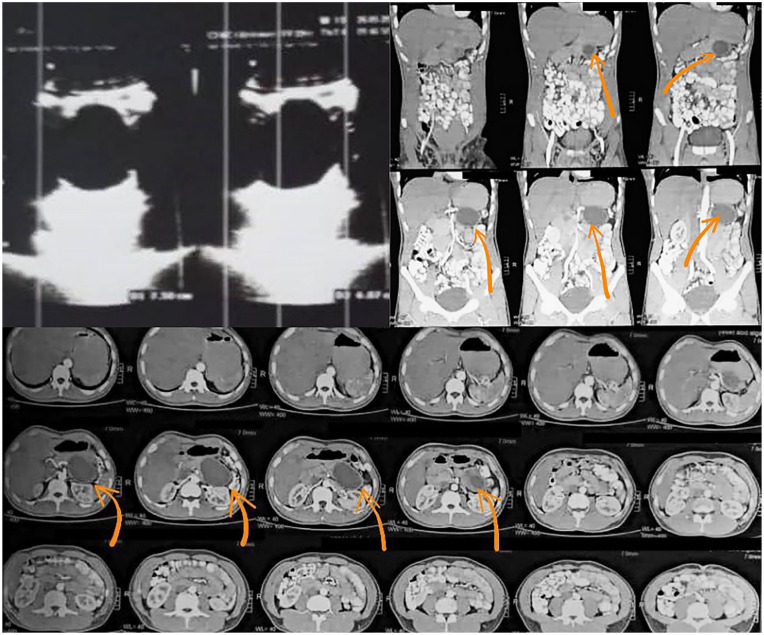

Case presentation: A 42-year-old man with a cystic lesion in his pancreatic tail who had no notable medical history was seen. The diagnosis of a pancreatic hydatid cyst was validated by serological testing and diagnostic imaging techniques.

Clinical discussion: Due to their uncommon nature, the differential diagnosis of pancreatic hydatid cysts can be challenging. Imaging modalities such as computed tomography (CT), magnetic resonance imaging (MRI), and ultrasound are important for identifying characteristic features. Serological testing further aids in confirming the diagnosis. Treatment typically involves a combination of medical and surgical approaches. Antiparasitic drugs, such as albendazole or mebendazole, are administered to kill the parasite. Surgical intervention is necessary to remove the cyst and reduce the chance of recurrence and complications.